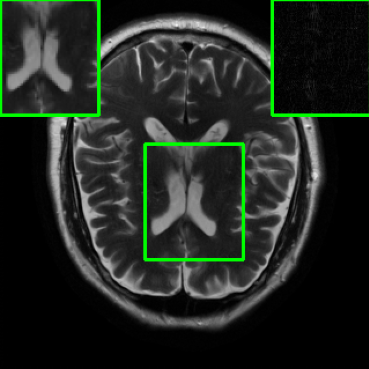

| Ground Truth | Initial | Global | LONDN-MRI | LONDN-MRI | Oracle |

| (1 iteration) | (2 iterations) | ||||

![]() |

| PSNR = dB | PSNR = 19.41 dB | PSNR = 26.52 dB | PSNR = 27.76 dB | PSNR = 27.85 dB | PSNR = 27.92 dB |

Performance on the Stanford FSE Dataset: We also performed image reconstructions with the Stanford multi-coil FSE dataset, which is a smaller dataset. We used same settings for the networks and training as in Section IV-A. Table III shows that LONDN-MRI significantly outperforms the globally learned MoDL network at both 4x and 8x acceleration. This indicates benefits for the proposed framework for smaller, more diverse datasets. Figs. 7 and 8 display visual comparisons that show the LONDN-MRI scheme recovering sharper features than the globally learned network.

| Acceleration | Global | LONDN-MRI | LONDN-MRI | Oracle |

|---|---|---|---|---|

| (1 iteration) | (2 iterations) | |||

| 29.45 | 31.49 | 31.56 | 31.67 | |

| 27.25 | 29.35 | 29.43 | 29.60 |